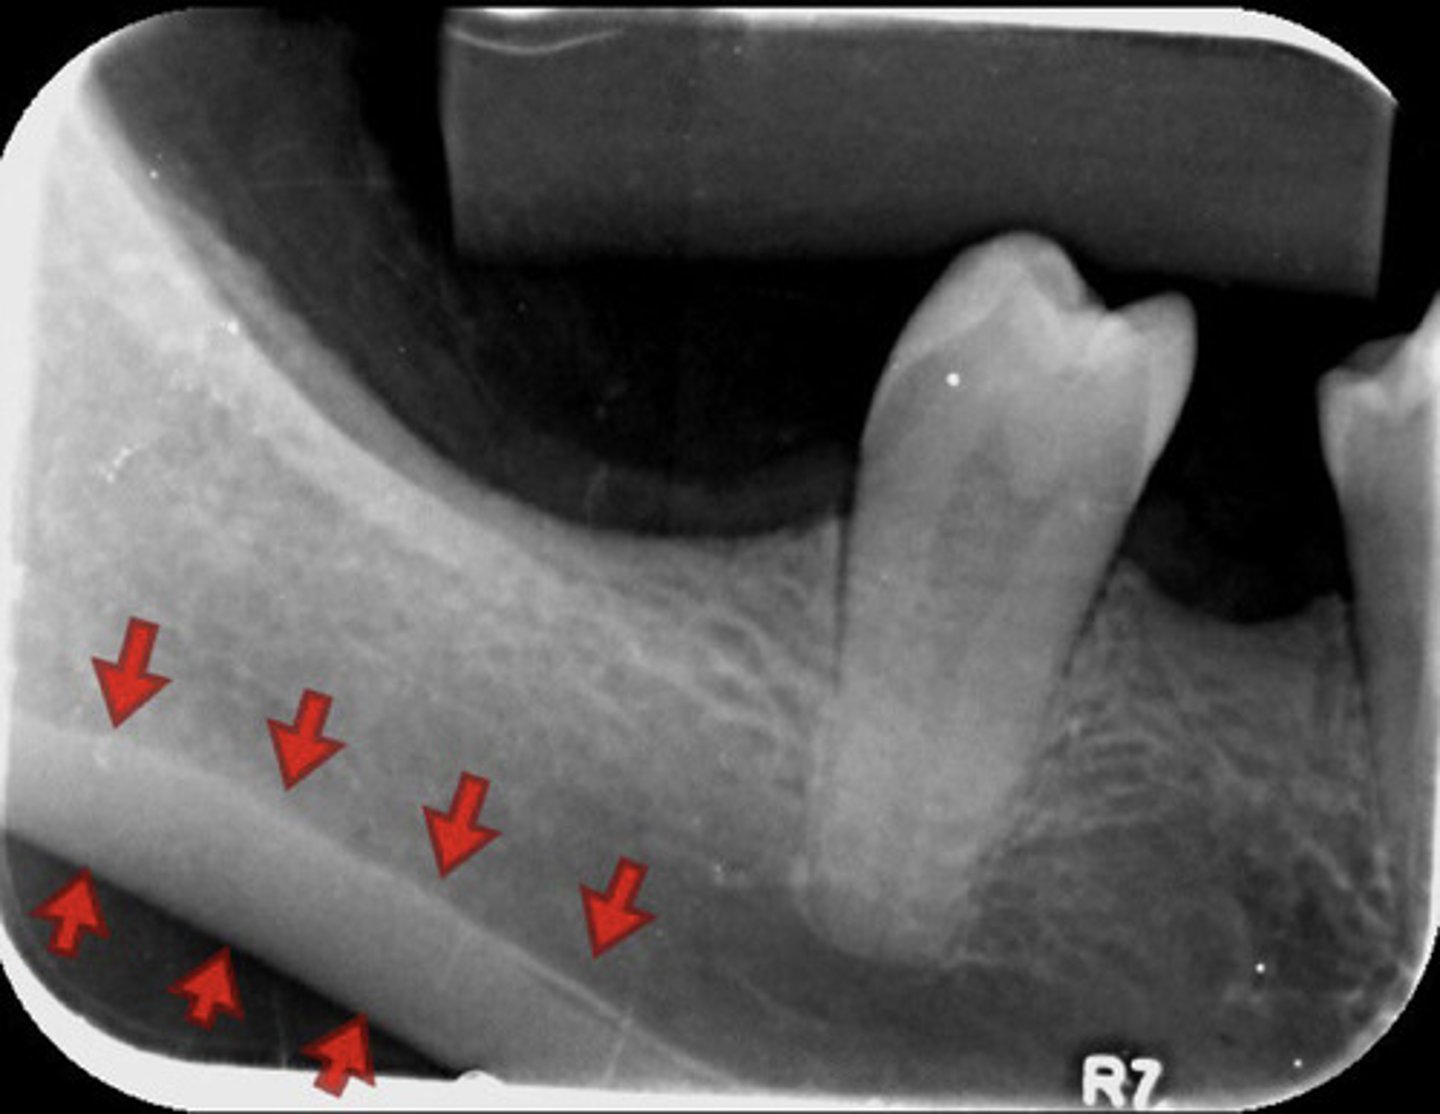

information on mandibular canal

radioluncentt band, with two thin radiopaque line & below the apices of the mandibular molar teeth

1. external oblique

2. Inferior oblique (mylohyoid ridge)

3. mandibular canal

4. mandibular gland fossa

5. inferior border of mandible

information on mylohyoid ridge

dense radiopaque band that extends downward and forward from the third molar region at the level of the apices of the posterior teeth

information on external oblique ridge

appears as a radiopaque band extending downward and forward from the anterior border of the ramus of the mandible

-starts behind last tooth and comes forward

information on submandibular gland fossa

radiolucent area in the molar region below the mylohyoid ridge

What does the inferior border of the mandible look like radiographically?

information on inferior border of the mandible

radiopaque band of bone

-only see if there is a lot of angulation